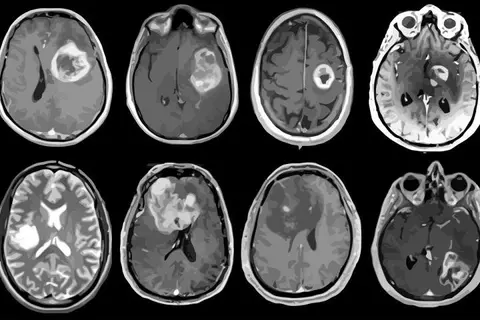

Al presentar casos presentados en ese centro de salud, informó que los principales tumores que se producen son tumores cerebrales dentro del cerebro y los producidos en el tejido:

Díaz, con estudios especializados en Francia, dijo que los que salen del tejido cerebral pueden ser benignos y hasta altamente malignos, llamados gliomas grado 4, lo que consideró los verdaderos cánceres cerebrales.

Sostuvo que los tumores de las envolturas del cerebro han observado aumento importante en metástasis.

“Se observa incremento en los últimos años, no porque haya más tumores, sino porque tenemos más facilidades de diagnóstico con el aumento de los medios diagnósticos, como tomografía, resonancia magnética y estudios angiográficos”, precisó.